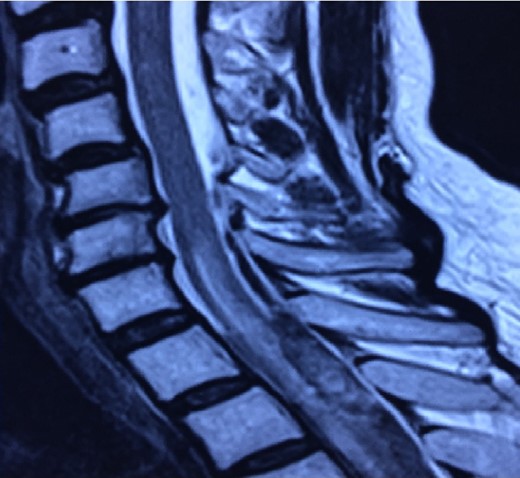

Patient is taken to the operating room immediately, where a wide laminectomy was performed from T4 to T7, durotomy and drainage of subdural hematoma (Figs 3 and 4). No complications during surgery.

Decompressive laminectomy and surgical drainage of the hemorrhage is the treatment of choice [1, 3, 9]. Prompt surgical intervention is necessary to avoid a permanent neurological deficit. Spontaneous resolution of intraspinal hematomas is rarely documented. Conservative treatment is a viable option when neurological symptom severity is grade D or E in the Frankel Scale. Surgeon criterion is advised on every individual case as surgical intervention augments the risk of iatrogenic spinal cord injury and excessive bleeding in those under anticoagulant therapy [8, 10]. Nonetheless, operative treatment is a necessary risk when a severe neurological deficit is evident and, more importantly, corrigible.